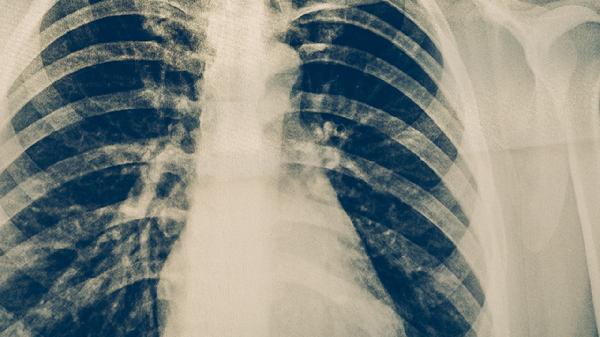

肺结核患者需遵医嘱使用异烟肼片、利福平胶囊、吡嗪酰胺片、乙胺丁醇片、链霉素注射液等抗结核药物联合治疗。肺结核是由结核分枝杆菌感染引起的慢性传染病,规范用药是治愈的关键。

肺结核患者应坚持足疗程规范用药6-9个月,不可自行停药或减量。治疗期间需每月复查痰涂片和胸片,保持高蛋白高维生素饮食,适当进行呼吸功能锻炼。注意隔离防护避免传染他人,居住环境要通风良好,餐具需煮沸消毒。出现药物不良反应应及时就医调整方案,全程治疗需在结核病专科医生指导下进行。